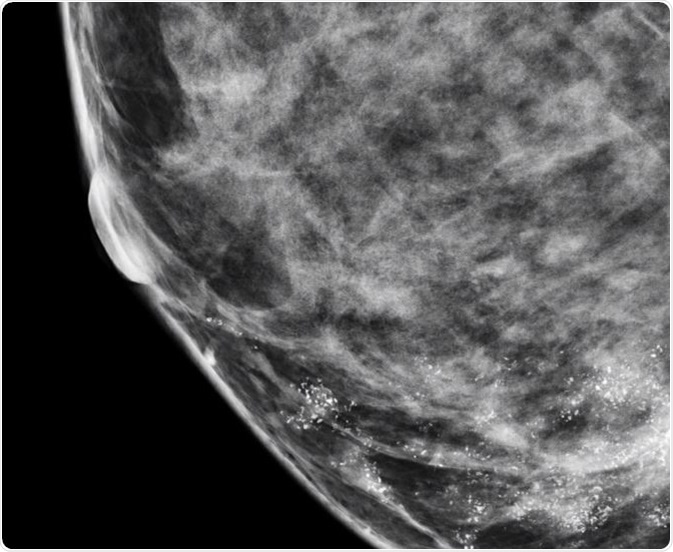

Microcalcifications in Breast

Microcalcifications are actually calcium deposits and are seen as tiny, white dots on a mammogram. They are much less common and are mostly a result of mutations in the breast tissue, though they can be caused by other factors. The appearance of microcalcifications is widely used in the detection of breast cancer at an early stage and can lead to better outcomes.

In general, when the distribution of microcalcifications is diffuse or bilateral, when they have a round and/or punctuate shape, or when they are scattered in the breast tissue, the condition is usually benign. On the other hand, if microcalcifications have a linear or branching pattern with irregular borders, or if they have variable density, or when they are distributed in a haphazard or segmental way, there is a high probability that it is ductal carcinoma in situ or malignant cancer.